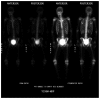

Burkitt lymphoma is a highly aggressive form of Non-Hodgkin lymphoma that responds favorably if diagnosed accurately and treated early. Recognition of the various radiologic manifestations of Burkitt lymphoma can help guide the clinician to expedite appropriate chemotherapy. We present two cases that illustrate different radiologic presentations of this aggressive gastrointestinal malignancy in children. Case 1 features a 7-year-old boy who presented to our hospital with recurrent ileocecal intussusception. Case 2 describes a 16-year-old male with history of blood-streaked stools. Ileocectomy was performed in both cases and histologic analysis showed the "starry sky pattern" and t(8;14) translocation, classic for Burkitt lymphoma. Both patients remain disease-free following surgical excision and chemotherapy.